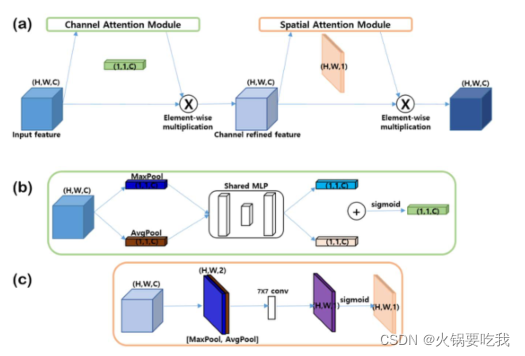

CBAM(convolutional block attention module )结构:通道注意力模块+空间注意力模块

multi-layer-perceptron(MLP)